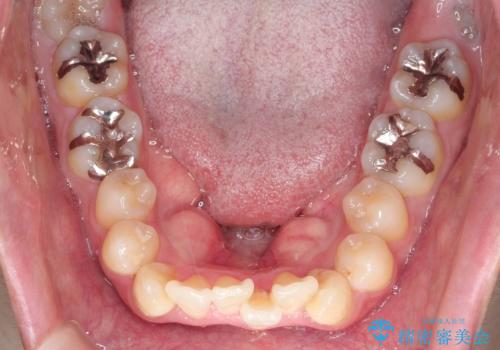

- 「歯のデコボコと前歯が引っ込んでいるのを治したい」を主訴に来院された患者様です。

デコボコの量が多かったため上下左右4を抜歯してワイヤー矯正で治療を行いました。

正面から見たときに右上2が全く見えないくらい、右上2が後ろに引っ込んでいる状態でしたが綺麗に並べる事が出来ました。